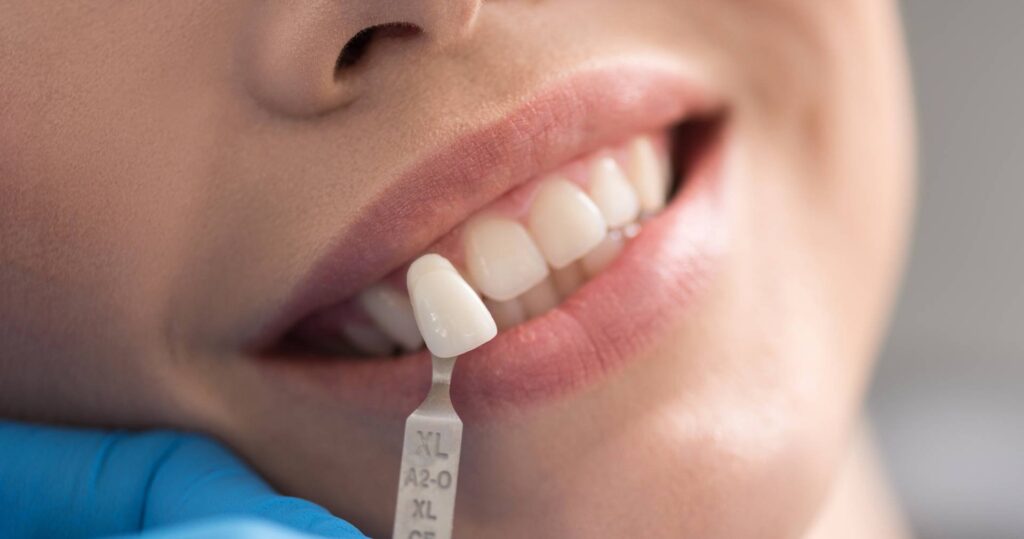

陶瓷貼片如何打造嶄新笑容?

對平常專注在補綴贗復(就是針對牙齒本身外觀的復型)的牙醫師而言,貼片或是3D齒雕其實都只是一種利用陶瓷材料恢復牙齒外型的技巧,而這些療程因為可以重新整體考量患者的需求,透過數位設計達到量身定做,所以適用在許多想改變自身牙齒外觀的案例。

初次看診除了口腔內的影像紀錄(包含X光片與臉部掃描),我們也會依照個人的唇形、膚色,甚至是平常的妝容做評估。事實上很多人會忽略,牙齒排列的牙弓形狀與嘴唇的豐隆度,也是影響笑容很重要的關鍵!